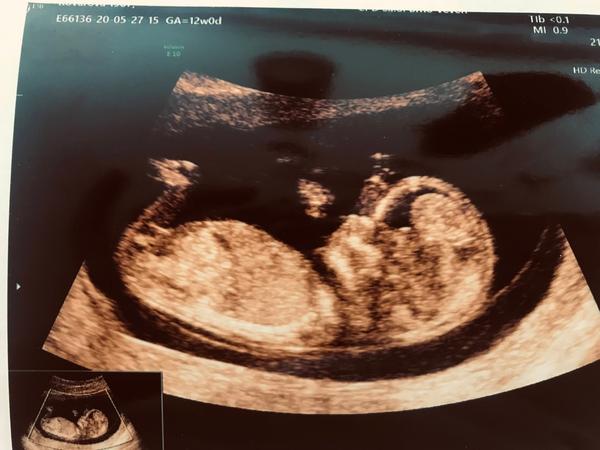

Ahoj 🙋♀️ máte prosím nějaký tip? Fotka je z 12+2,dekuji 😊

@kopretina93 tipuju holcicku